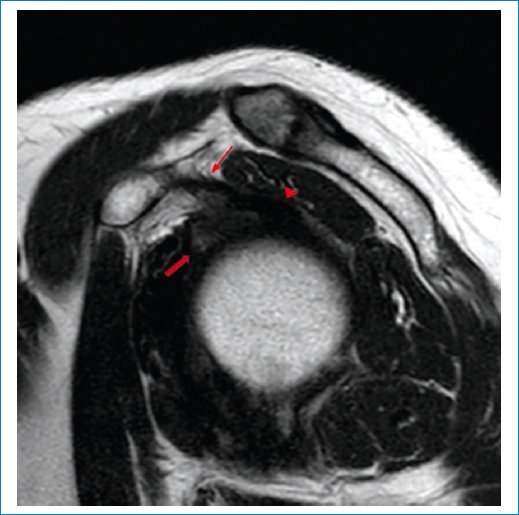

En nuestra serie aplicamos los criterios de Emig et al.11, que incluyen la hiperintensidad o el engrosamiento del ligamento glenohumeral inferior > 3 mm (Figs. 1 a 3), el engrosamiento capsular del receso axilar (con valores que varían según los estudios, pero descrito en general como > 7 mm) (Fig. 3), el engrosamiento del ligamento coracohumeral > 4 mm (Fig. 4), la infiltración grasa y la hiperintensidad del intervalo rotador (Figs. 5 a 7), y la obliteración de la grasa subcoracoidea (descrita como ausente, parcial o completa) (Fig. 8).

Figura 4. RM en secuencia DP, corte sagital. Se observan el ligamento coracohumeral (flecha gruesa) y el tendón del bíceps braquial (flecha fina).

Figura 5. RM en secuencia potenciada en T2, corte sagital. Se observan obliteración parcial del intervalo rotador (flecha gruesa), engrosamiento del ligamento coracohumeral (flecha fina) y bíceps braquial (punta de flecha).